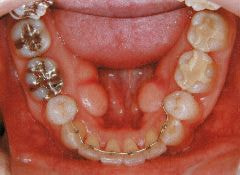

治療例2 (補綴処置+矯正)